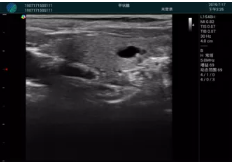

可視化穿刺引導(dǎo)

M20實(shí)時引導(dǎo):向包塊后方間隙注射利多卡因

清晰顯示腺體內(nèi)低回聲快影,邊界清晰,包膜較光滑

確定進(jìn)針路徑并實(shí)時監(jiān)測抽吸針與腫塊位置關(guān)系

抽吸針進(jìn)入腫塊內(nèi)部進(jìn)行旋切

抽吸過程中可見腫塊明顯縮小,并根據(jù)腫塊位置改變針道位置

抽吸旋切后再進(jìn)行超聲復(fù)查,原腫塊區(qū)域未見殘留組織及出血

超聲引導(dǎo)下抽吸旋切取出的腫塊組織